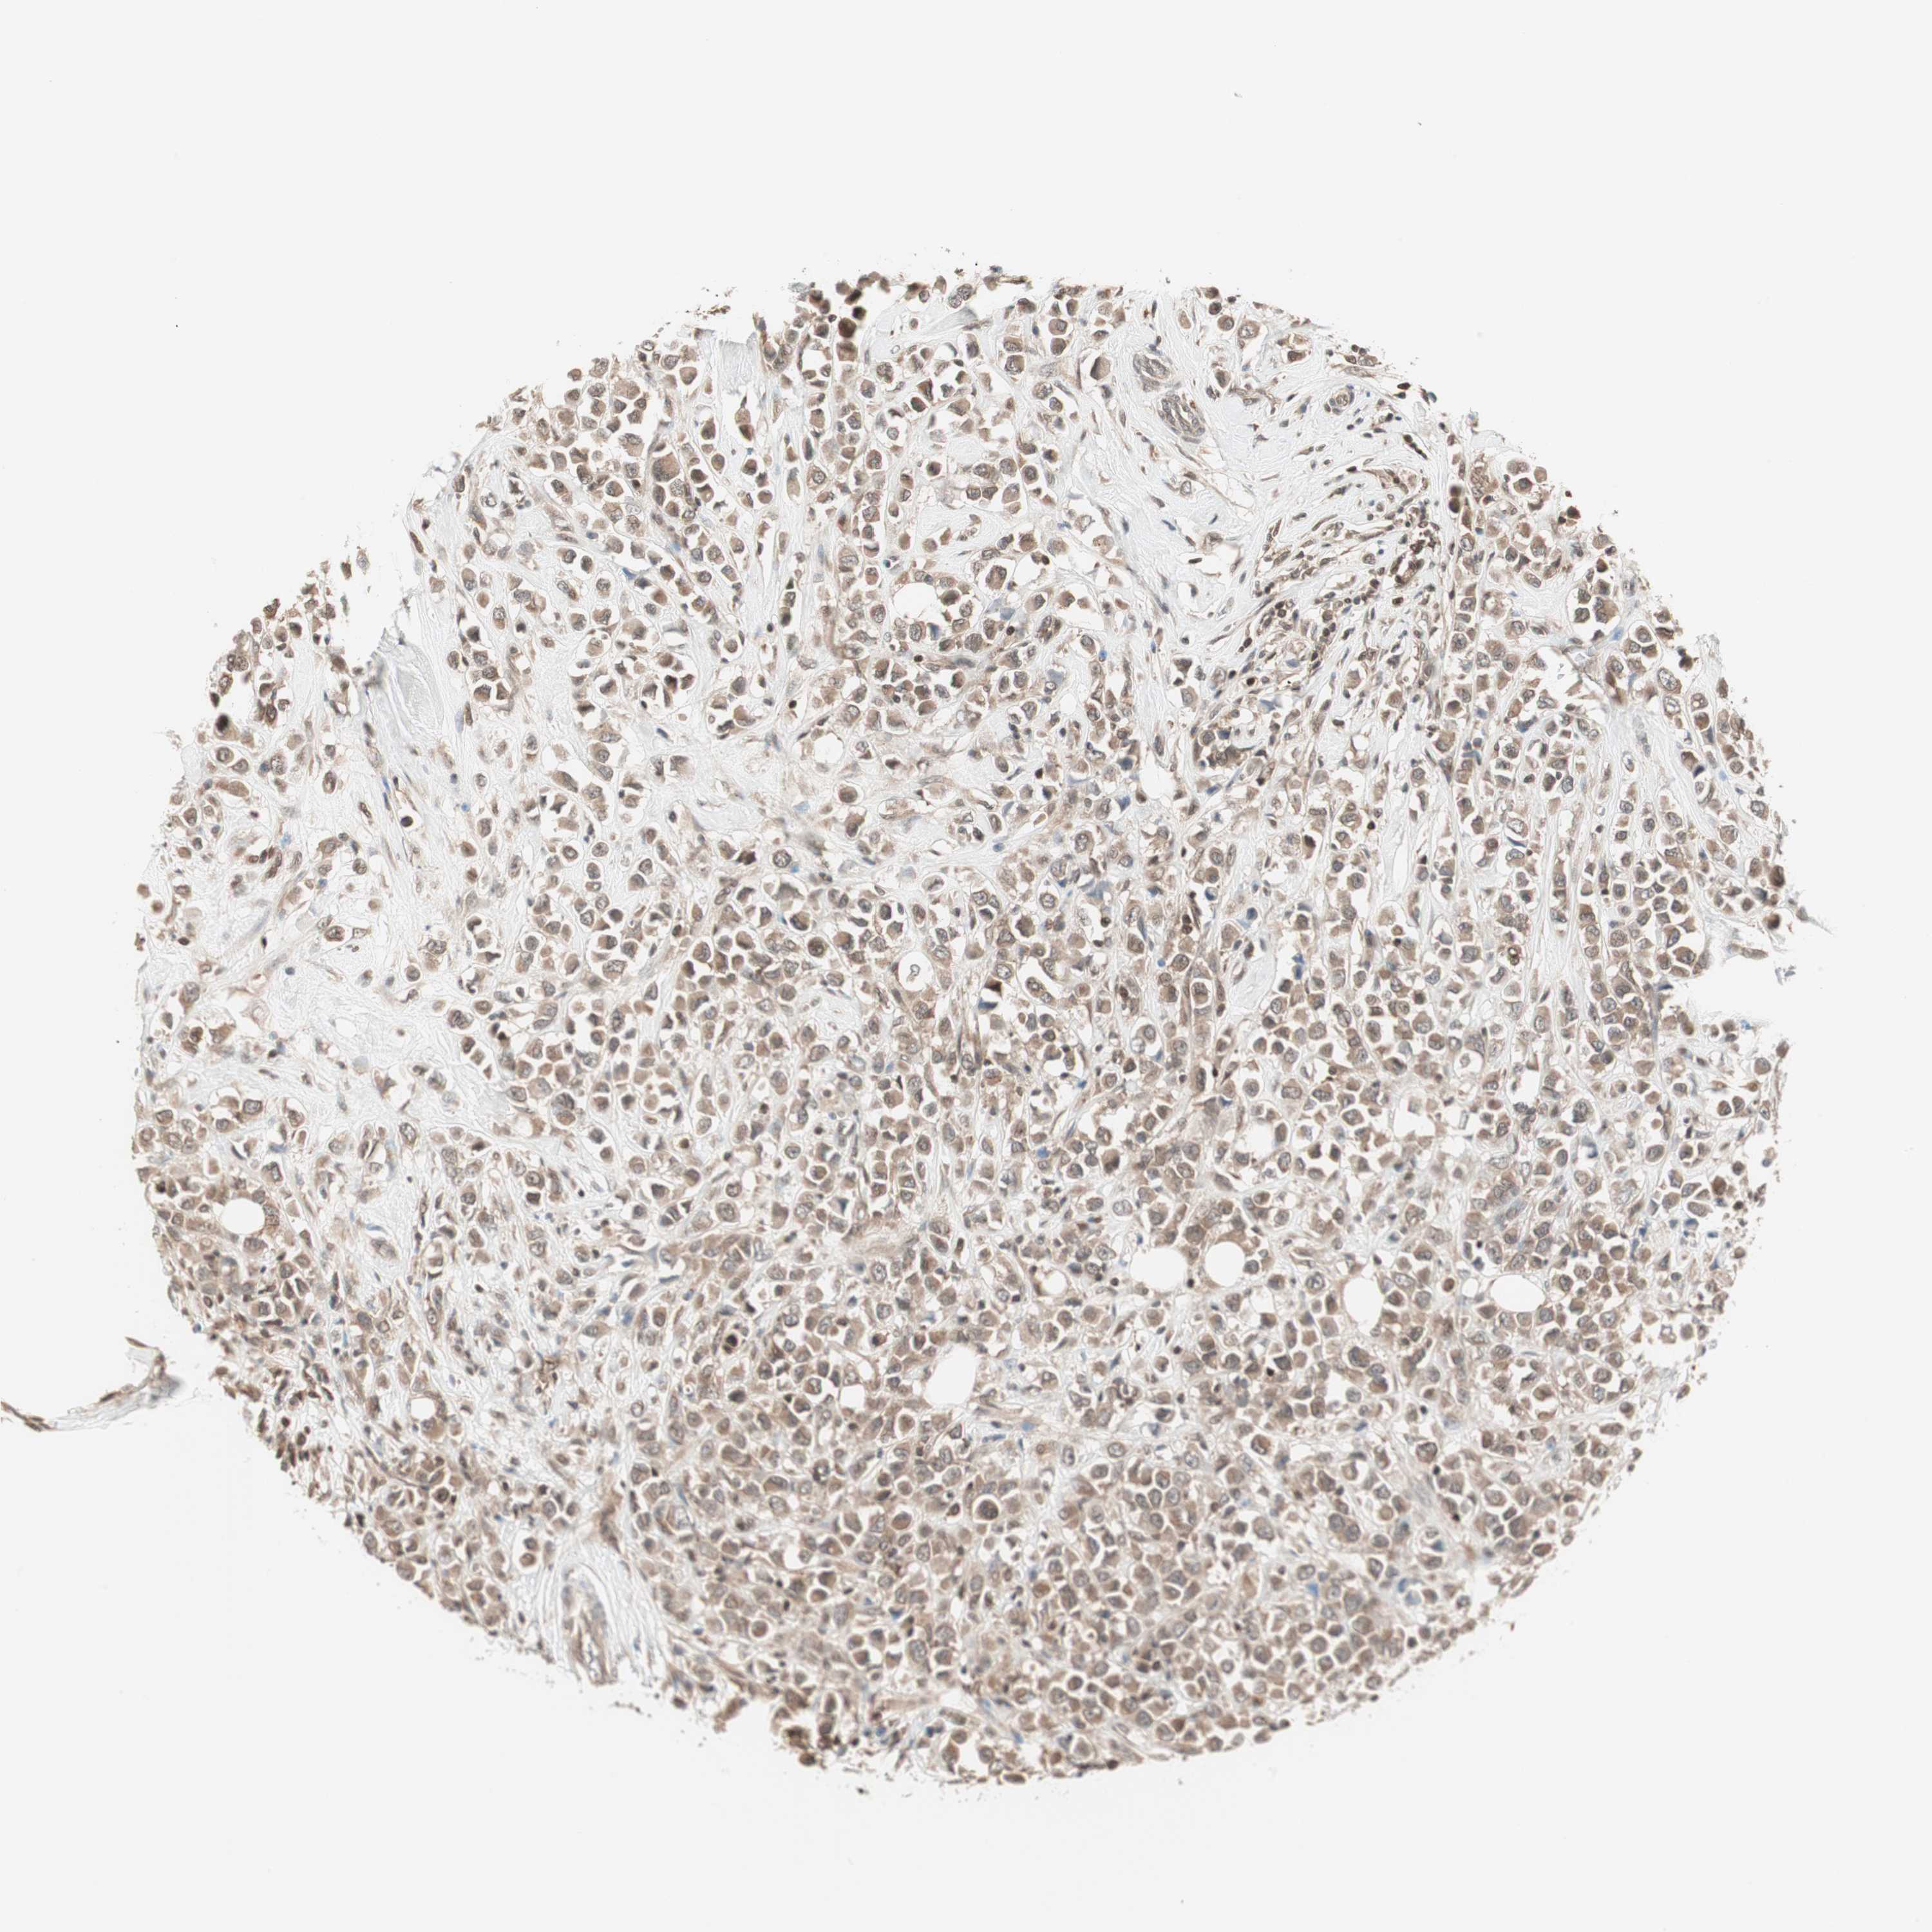

CANCER BREAST CANCER Show tissue menu

BRCA TCGA BRCA VALIDATION PROTEIN EXPRESSION